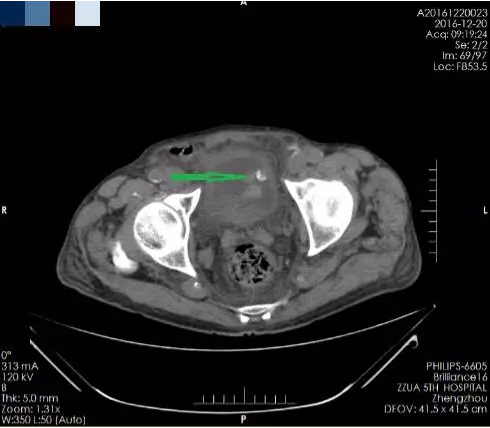

箭头所指为膀胱肿瘤